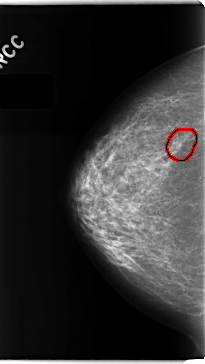

C_0151_1.RIGHT_CC

LEFT_CC LINES 4728 PIXELS_PER_LINE 2584 BITS_PER_PIXEL 12 RESOLUTION 50 NON_OVERLAY

FILE: C_0151_1.RIGHT_CC.OVERLAY

TOTAL_ABNORMALITIES 1

ABNORMALITY 1

LESION_TYPE CALCIFICATION TYPE PLEOMORPHIC DISTRIBUTION CLUSTERED

ASSESSMENT 4

SUBTLETY 3

PATHOLOGY MALIGNANT

TOTAL_OUTLINES 1